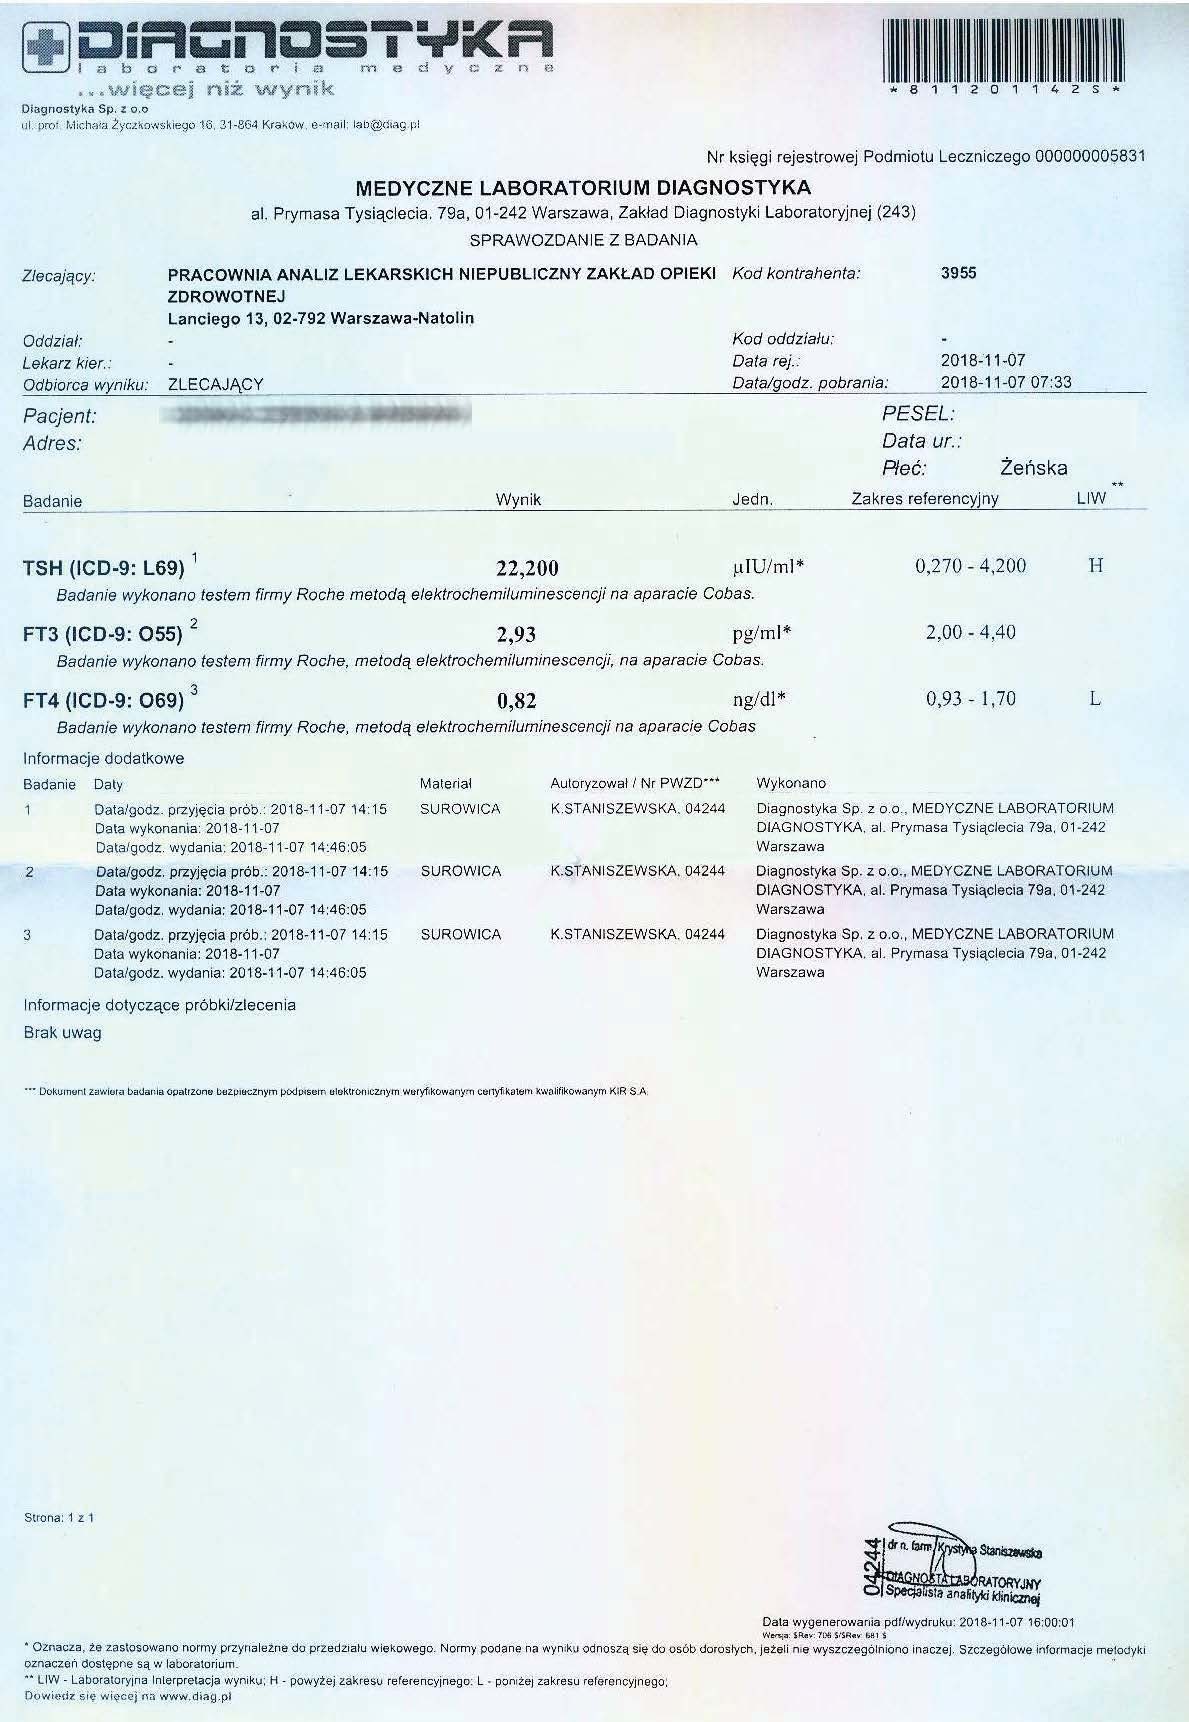

PRZYKŁAD EFEKTU PREPARATU NA NIEDOCZYNNOŚĆ TARCZYCY

Kobieta lat 59 z niedoczynnoscią tarczycy, bez przyjmowania lewotyroksyny. Kobieta przyjmowała preparat przez okres ponad 3 miesięcy. Przy zachowaniu naturalnego cyklu komórkowego i stałemu stymulowaniu mitochondriów osiągneła następujące wyniki kuracji:

Po zaobserwowaniu znacznej poprawy w ogólnym samopoczuciu, kobieta postanowiła wykonywać badania ze zwiększoną częstotliwością oraz kontrolę prób wątrobowych.

Po kolejnych dwóch miesiącach kobieta ponownie wykonała badania. Widoczne są: spadek TSH, obniżenie stanu zapalnego jak i spadek markeru wątrobowego GGTP.

Sukcesywnie co 2 miesiące można zaobserwować stały spadek parametrów zarówno wątroby jak i tarczycy. Kolejne badania potwierdzały dalszy spadek parametrów.

Po ponad roku kuracji badania wykazały dalszy postęp wycofania autoimmunologi tarczycy, potwierdzone również badaniem USG narządu.

Preparat wpływając na odbudowę mitochondriów zapewnił podłoże energetyczne do produkcji hormonów i odbudowy narządu. Brak ingerencji farmakologicznej wykazuje skuteczność nawet w podeszłym wieku, gdzie regeneracja jest wolniejsza a reakcje anaboliczne w znacznym stopniu spowolnione. Można zaobserwować także działanie ogólnoustrojowe obserwując spadek markeru wątroby, co jasno wykazuje poprawę funkcjonowania całego organizmu.